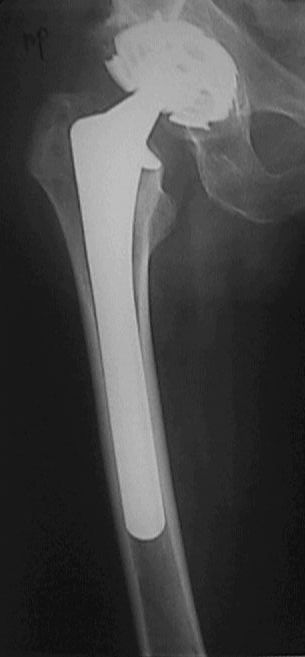

Перелом бедра с эндопротезом

Больной оперирован в конце марта 2003 НИИТО г. Новосибирск. Не замечен перелом бедра р-ма 1.- 2 . (сделанных в НИИТО).

Больному рекомендовали ходить приступая на конечность, отмечает усиление болей, появление укорочения. На контрольных рентгенограммах 19.05.03 рис 3 имеется перелом бедра со смещением, появлением периостальной мозоли. Больной ходит на костылях, приступая на конечность. Сгибание в т\б суставе 90 гр , сгибание в коленном суставе до 90 гр в положении стоя на костылях. Есть несколько вариантов. 1. Провести открытую репозицию фиксацию пластиной с проведением винтов на уровне ножки протеза через кортикальный слой. 2.Провести открытую репозицию фиксацию винтами с межфрагментарной компрессией. Думаем, как выполнить репозицию перелома по длине. 3. Наложить кокситную повязку до окончательного сращения перелома 4. Провести скелетное вытяжение репозицию. Сергей Зырянов Новосибирская область г. Куйбышев ЦРБ